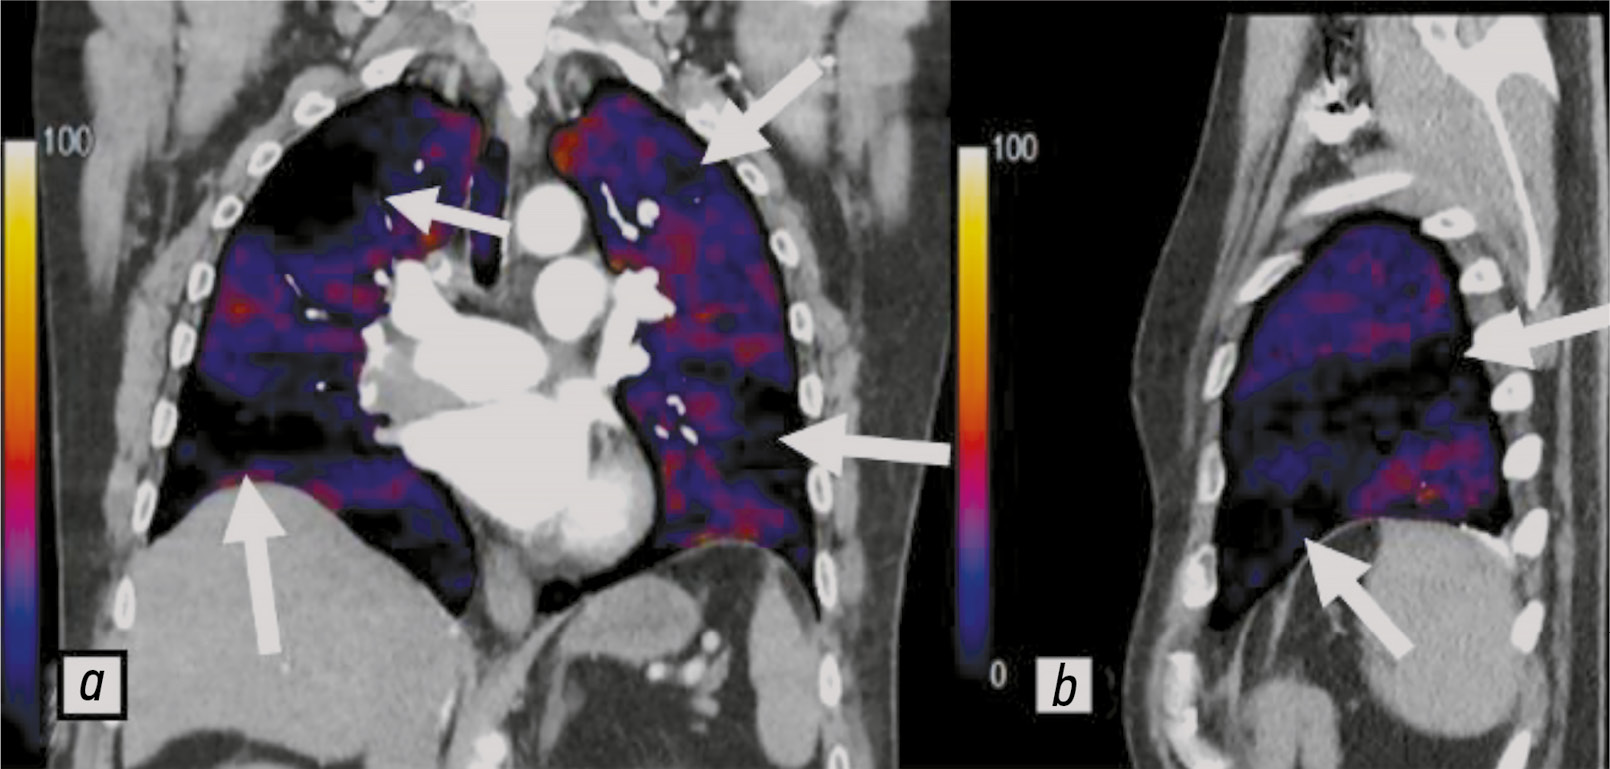

Ещё одним методом оценки микроциркуляторного русла является субтракционная КТ-ангиопульмонография с дальнейшим построением йодных карт. Метод основан на вычитании неконтрастных изображений из изображений с контрастированием, что позволяет визуализировать сосудистую систему лёгких. Сканирование пациента проводят два раза с помощью одноэнергетической компьютерной томографии: первое — нативное; второе — с введением контрастного препарата. Лучевая нагрузка составляет в среднем 11,2±4,7 мГр [52]. С целью снижения лучевой нагрузки первое сканирование можно проводить в низкодозовом режиме. Субтракционные йодные изображения позволяют осуществлять диагностику ХПЭЛГ в некоторых медицинских учреждениях стран Европы и Азии. L. Shahin и cоавт. [52] утверждают, что с их помощью возможно определить йод в паренхиме с большей чувствительностью, чем при двухэнергетическом сканировании. Цветовая шкала на йодных субтракционных изображениях имеет диапазон по умолчанию от 0 до 100 HU4. Чёрные участки соответствуют отсутствию перфузии, а тёмносиние — снижению перфузии (рис. 4).

Рис. 4. Перфузионные йодные карты, полученные с помощью субтракционной компьютерно-томографической ангиопульмонографии: a — клиновидные дефекты перфузии во фронтальной проекции (белые стрелки); b — клиновидный дефект перфузии в сагиттальной проекции (белые стрелки). Публикуется с разрешения правообладателя. © ФГАУ «Лечебно-реабилитационный центр», 2018.

Хорошие результаты получены в научном исследовании при сравнении мультидетекторной и субтракционной КТ-ангиопульмонографии с получением йодных изображений, при этом за референсные значения принимали результаты сцинтиграфии лёгких [25]. Субтракционные изображения показали более высокие диагностические характеристики (чувствительность и специфичность — 95 и 84% соответственно) по сравнению с одноэнергетической компьютерной томографией без оценки перфузионных изображений (чувствительность и специфичность — 65 и 61% соответственно) [52].

В большинстве случаев доля ложноположительных и ложноотрицательных результатов составляет ~2% общего количества исследований. Согласно ретроспективным данным, основная причина несоответствия связана с различием в интерпретации участков гипоперфузии и их локализации [25]. Артефакты от контрастированной верхней полой вены и движений пациента визуально определяют как дефекты перфузии. Во фронтальной проекции они выглядят как чёрные радиальные либо горизонтальные полосы, распространяющиеся также на другие структуры — средостение, рёбра и т. д., помимо лёгочной паренхимы.

На изображениях с выделением сосудов отчётливо визуализируются лёгочные артерии с высокой контрастностью и меньшим шумом, что позволяет идентифицировать артерии мелкого калибра. На реконструкциях с выделением лёгочной паренхимы сосуды определяют как тёмные участки, соответствующие бассейнам окклюзированных артерий (рис. 5).